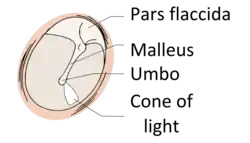

Regions

The eardrum is divided into two general regions: the pars flaccida and the pars tensa.[3] The relatively fragile pars flaccida lies above the lateral process of the malleus between the Notch of Rivinus and the anterior and posterior malleal folds. Consisting of two layers and appearing slightly pinkish in hue, it is associated with Eustachian tube dysfunction and cholesteatomas.[4]

The larger pars tensa consists of three layers: skin, fibrous tissue, and mucosa. Its thick periphery forms a fibrocartilaginous ring called the annulus tympanicus or Gerlach's ligament.[5] while the central umbo tents inward at the level of the tip of malleus. The middle fibrous layer, containing radial, circular, and parabolic fibers, encloses the handle of malleus. Though comparatively robust, the pars tensa is the region more commonly associated with perforations.[6]

Umbo

The manubrium (Latin: handle) of the malleus is firmly attached to the medial surface of the membrane as far as its center, drawing it toward the tympanic cavity. The lateral surface of the membrane is thus concave. The most depressed aspect of this concavity is termed the umbo (Latin: shield boss).[7]

When the eardrum is illuminated during a medical examination, a cone of light radiates from the tip of the malleus to the periphery in the anteroinferior quadrant, this is what is known clinically as 5 o'clock.